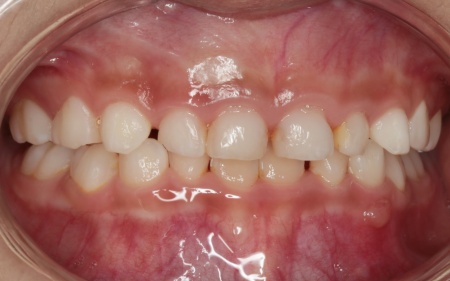

治療後

治療中は、スクリューを少しずつ回すことで顎の骨が徐々に横方向に拡大されていき、永久歯が生えるためのスペースを十分に確保することができました。

拡大治療が完了したあとは、顎の状態を安定させるためのリテーナー(保定装置)を装着し、治療を終了しています。